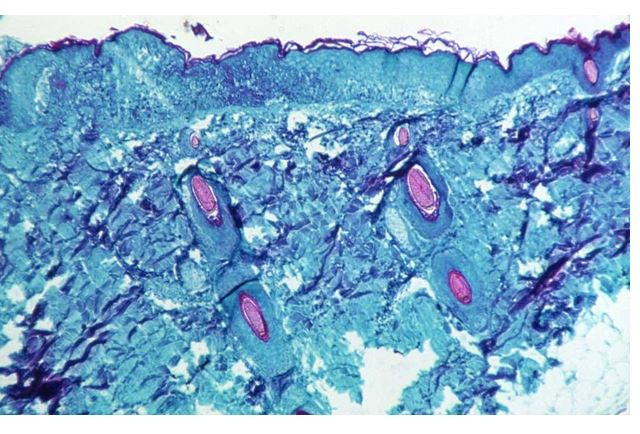

এ ছাড়া, এটা কোভিডের মত বেশিরভাগ ক্ষেত্রে মৃদু বা উপসর্গহীন নয়। বরং মাঙ্কিপক্সে আক্রান্ত হলে শরীর খারাপ করবে এবং শরীরে ফোস্কার মত গোটা দেখা দেবে। তাই কেউ এ রোগে আক্রান্ত কিনা সেটা জানতে পরীক্ষা পর্যন্ত অপেক্ষা করতে হবে না।